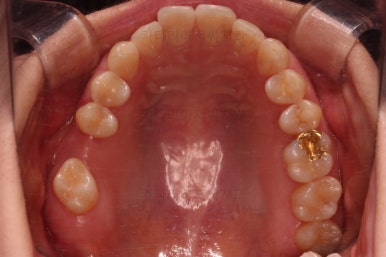

이번 환자분이 선택한 앞니 부분교정 장치는 MTA라는 장치인데요.

부분교정에 좀 더 특화된 부피가 작고 심미적인 장치입니다.

물론 철사는 들어가고요.

어금니쪽은 쓰러진 어금니를 원위치 시키기 위해서 미니스크류를 식립하여 준비작업을 해줍니다.

어금니 위치 조절을 계속 해주고요.

아래 앞니는 부분교정에 필수인 치간삭제를 병행하면서 많이 가지런해지고 있습니다.

진행상황을 X-ray로도 확인해 줍니다.

아랫니 부분교정이 끝났고요.

어금니도 원위치로 많이 갔네요.